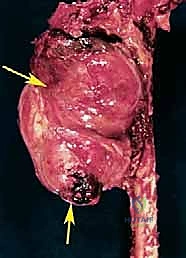

1. أورام العظام والأنسجة الرخوة الخبيثة (Sarcomas)

تُعد الأورام الخبيثة السبب الأكثر شيوعاً. وتشمل الساركوما العظمية (Osteosarcoma)، الساركوما الغضروفية (Chondrosarcoma)، وساركوما إوينغ (Ewing's Sarcoma). عندما يغزو الورم عظام الحوض، أو يحيط بالأوعية الدموية الرئيسية (الشريان والوريد الحرقفي) أو العصب الوركي، يصبح استئصال الورم مع الحفاظ على الطرف مستحيلاً.

باستخدام مناشير عظمية متقدمة، يتم فصل عظام الحوض عن العمود الفقري (عند المفصل العجزي الحرقفي) وفصلها من الأمام (عند الارتفاق العاني). يتطلب هذا دقة متناهية لضمان استئصال الورم بالكامل دون المساس بالأعضاء الداخلية في الحوض (مثل المثانة والمستقيم).

الخطوة الخامسة: إغلاق الجرح وإعادة البناء

بعد إزالة نصف الحوض مع الطرف السفلي، يتم غسل التجويف الجراحي بعناية فائقة. ثم يقوم الدكتور هطيف بسحب السديلة الخلفية (التي تم تحضيرها في الخطوة الثالثة) للأمام وتخييطها مع جدار البطن الأمامي. يتم وضع أنابيب تصريف (Drains) لمنع تجمع السوائل والدم.